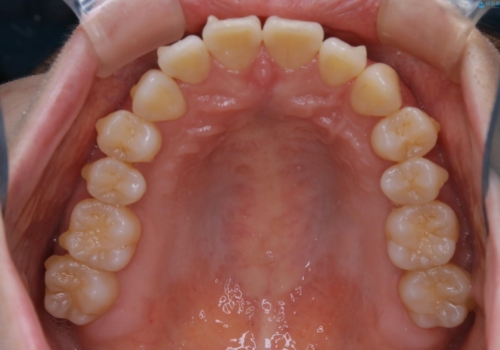

- 前歯のがたつきが気になるとご相談にいらした方です。右側前歯部のクロスバイトの他、左側にもシザーズバイトが認められたため、インビザラインにて治療を行いました。出産直後のため、ご自身の時間がなかなか取れないとの事で、最小限の来院回数で治療を勧められるように計画しました。

患者様ご自身で使用時間をしっかり管理して頂くことを条件に、最低限の来院回数で治療を進めていきました。20時間以上の使用を厳守して頂けたことで、少ない来院回数にて治療を終了することが出来ました。前よりも噛みやすくなったと大変喜んでいただけました。